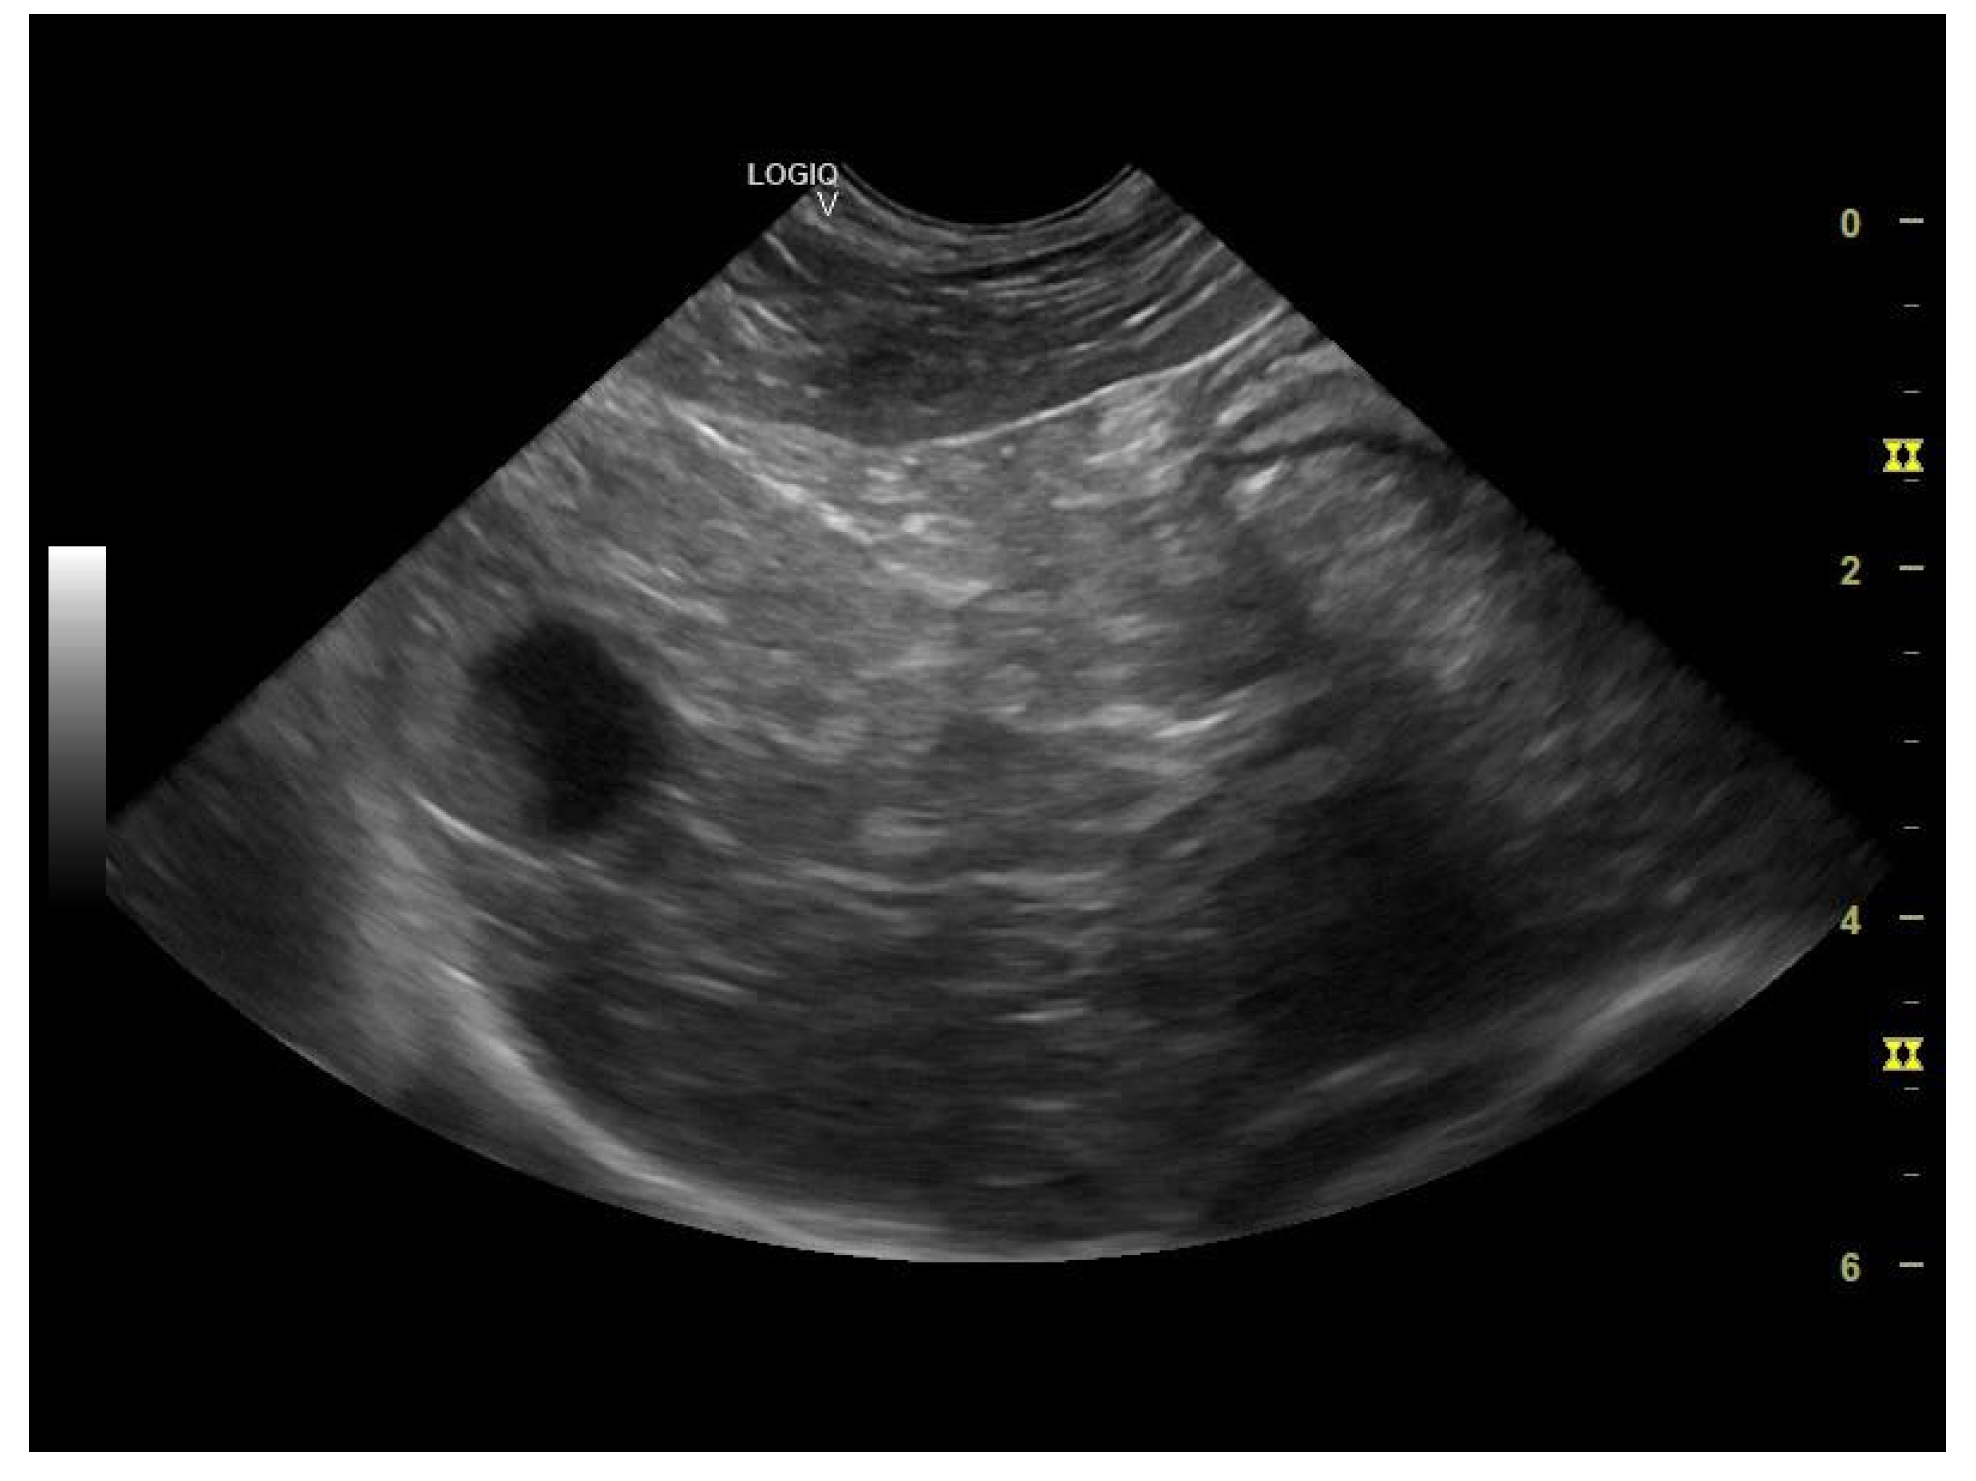

The liver appeared of normal size with non-homogeneous parenchyma, with multiple hyperechogenic strands diffusely dispersed throughout the parenchyma giving it a “Swiss cheese” appearance, with a slightly irregular outline and poorly distinguishable vascular walls (Figure 6 and Figure 7a,b). The gall bladder had a fine hyperechoic wall with anechoic content accompanied by hypoechoic, mobile, gravitationally dependent sediment in reduced quantity.

Figure 6. Liver and gallbladder—multiple hyperechogenic strands diffusely dispersed throughout the parenchyma—“Swiss cheese” appearance and gallbladder sediment (microconvex transducer).

The ultrasonographical aspect of the liver as well as the normal size of the organ combined with the Swiss cheese-like appearance of the parenchyma corroborates the diagnosis of hepatocutaneous syndrome. Another differential diagnosis in absence of the dermatological findings could have been that of chronic hepatitis/liver cirrhosis, although the liver is reported to be reduced in size in these common conditions.